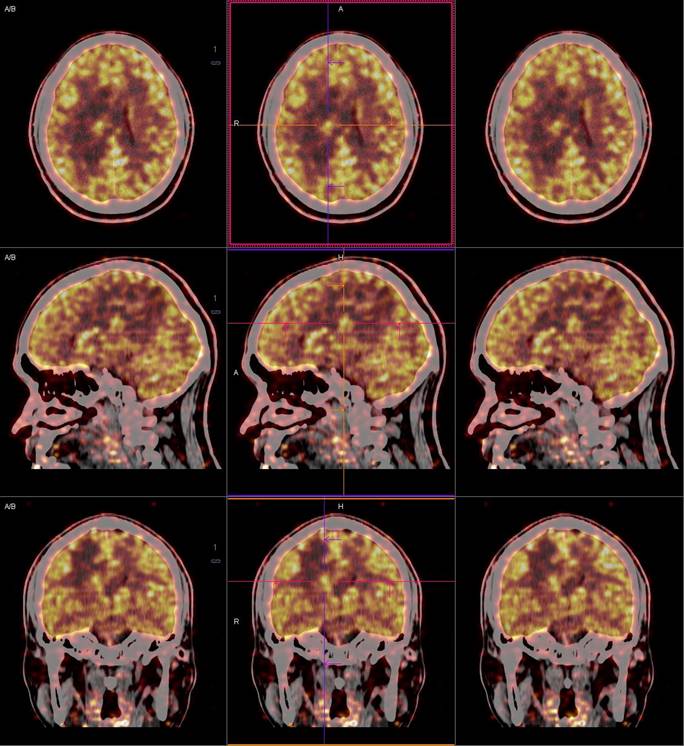

PET/CT影像圖

圖1

圖2

圖3

圖4

PET/CT檢查

影像診斷: 右側(cè)側(cè)腦室旁腦實質(zhì)內(nèi)結節(jié),代謝異常增高(SUVmax 12.13),伴瘤周水腫。

PET/CT鑒別診斷

正電子發(fā)射計算機斷層(positron emission tomography,PET)是一種分子成像技術,PET 應用 18F-FDG等顯像劑可顯示人體內(nèi)細胞、分子或者基因水平的生物學、病理學過程,進一步實現(xiàn)疾病早期定量與定性診斷。PET/CT使形態(tài)影像學與功能影像學得到了良好的結合,更有利于對腦膜瘤進行全面的評價。既往研究發(fā)現(xiàn),18F-DG PET/CT對診斷WHOⅠ、Ⅱ級腦膜瘤具有較高的敏感度,F(xiàn)DG攝取可用于評估腦膜瘤的腫瘤增殖情況,以此達到鑒別腦膜瘤的良、惡性的目的。有學者統(tǒng)計,WHOⅡ、Ⅲ級與 WHOⅠ級的平均標準化攝取值(standardized uptake value,SUV)分別為 2.51 (1.36,3.66)和 0.42 (0.12,0.73),WHOⅡ、Ⅲ級腫瘤與正常組織比率(T/N比率)存在差異,WHOⅡ級腦膜瘤的 SUVmax和最大T/N比率顯著高于 WHOⅠ級腦膜瘤。SUV和T/N比率對高級別腦膜瘤的診斷有較高的特異度。

此例,PET/CT全身檢查不僅排除了轉(zhuǎn)移瘤的可能性,增高的SUV值無創(chuàng)地鑒別腦膜瘤的良惡性,充分體檢PET/CT大視野、形態(tài)與功能影像結合的優(yōu)勢。